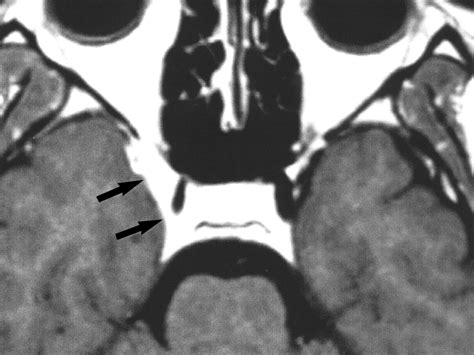

Diagnosing Cavernous Sinus Syndrome requires a high index of clinical suspicion and advanced imaging techniques. Physicians often utilize a combination of clinical evaluation and diagnostic testing to pinpoint the underlying etiology. Because the syndrome can be caused by various factors—from infections like sinusitis to malignant tumors or cavernous sinus thrombosis—the approach must be comprehensive.

MRI (Magnetic Resonance Imaging) Provides detailed views of soft tissues, identifying tumors, aneurysms, or inflammation.

CT Scan (Computed Tomography) Excellent for viewing bone involvement, particularly if the cause is related to paranasal sinus infection.